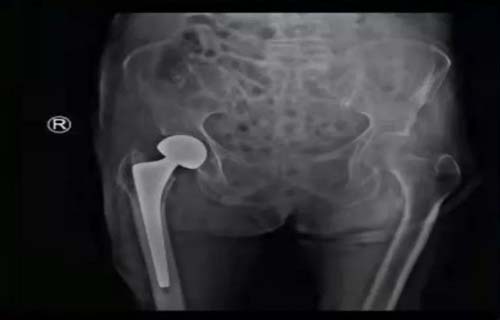

患者超高龄,既往有胃炎病史,平日经常恶心,进食少,消瘦,营养状况欠佳,入院后术前化验检查示贫血、低蛋白血症、凝血障碍、心功能不全及肺部感染。为最大限度地帮助老人恢复部分生活自理能力,减轻痛苦,改善生活质量,以创伤中心常务副主任李连欣为首的专家团队,经过充分的术前检查及多科讨论,认为老人手术指征强,意义重大,虽有风险,但总体可控。经与家属沟通同意后,创伤中心首席专家周东升教授为老人施行了“人工股骨头置换术”。为加强术后监护及精细化管理,老人术后转入东院创伤四科(创伤重症病房)。

个体化、多模式联合镇痛、止吐、化痰、纠正贫血、营养支持、维持水电解质平衡,每一种药物、每一毫升液体、每一步治疗措施都严格缜密的计算。护理团队积极实施心理支持、皮肤护理、体位及气道管理、肢体康复锻炼等综合干预措施。老人在医护团队的共同努力下,平稳度过了术后的各种危险期,肢体功能也逐渐恢复,生活质量得到极大改善,老人顺利康复出院。

出院1周后回访,邹奶奶在家已经下床使用助行器走路了,邹奶奶及家属对治疗效果很满意,对医护团队的努力付出,表示深深地感谢!